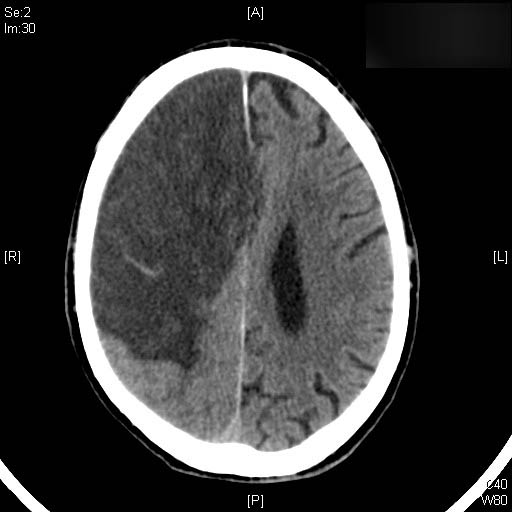

AVC amplio de territorio de A. cerebral media

Hematoma subdural por caída.